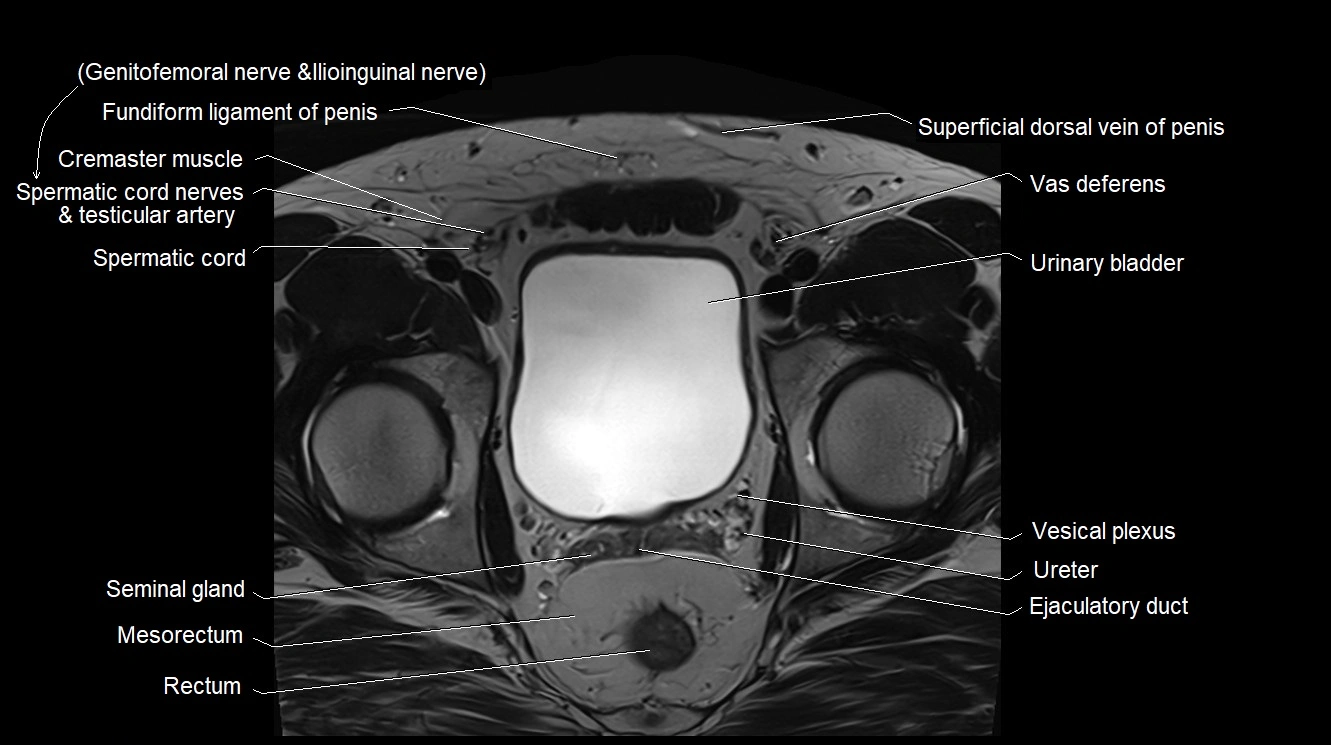

MRI image